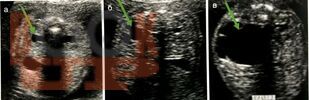

Учебное пособие полностью соответствуют требованиям ФГОС ВО по специальности 31.05.02 Педиатрия. Данное учебное пособие посвящено вопросам клиники, ранней диагностики и лечения врождённых обструктивных уропатий у детей. Учебный материал адаптирован к образовательным технологиям с учетом специфики обучения на педиатрическом и лечебном факультетах. Пособие иллюстрировано рисунками и рентгенограммами, имеются ситуационные задачи и тестовые задания.